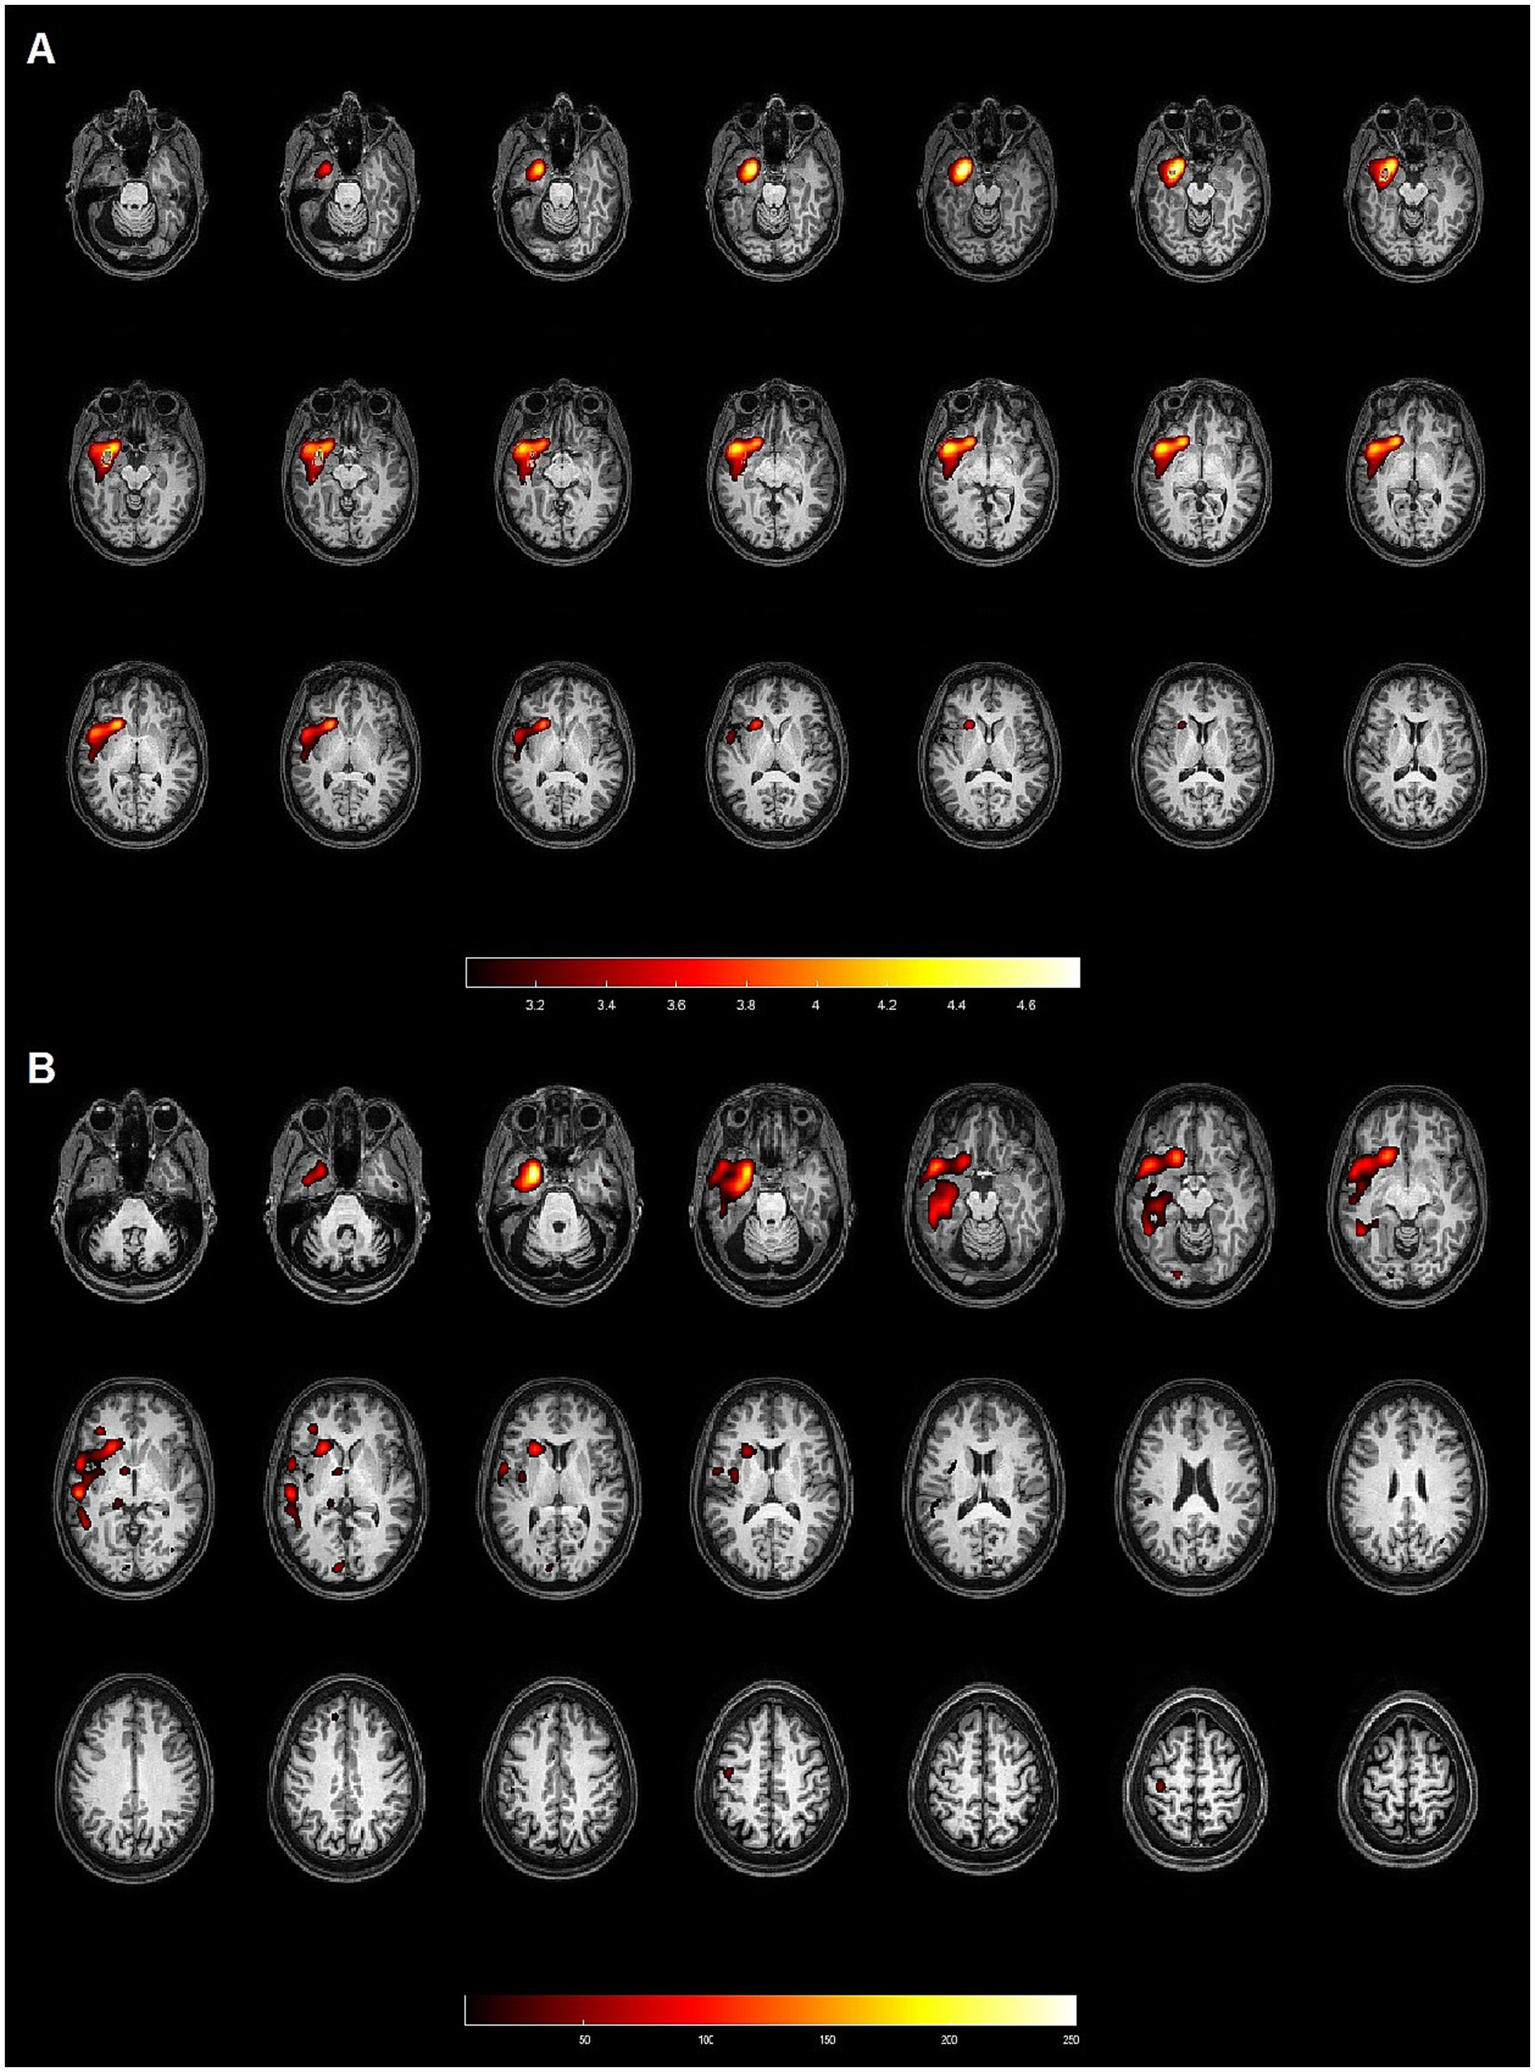

Figure 1

Patient 4: 50-year-old female with left hippocampal sclerosis. Both methods (SPM and Analyze) demonstrated concordance with the gold standard, identifying the EZ in the left temporal lobe. (A) Axial slices from the SISCOM analysis using SPM, showing the largest cluster and the voxel with the highest intensity located in the left temporal lobe, concordant with the EZ. (B) Axial slices from the Analyze software, also identifying the largest cluster and the voxel with the highest intensity in the left temporal lobe, both concordant with the EZ.